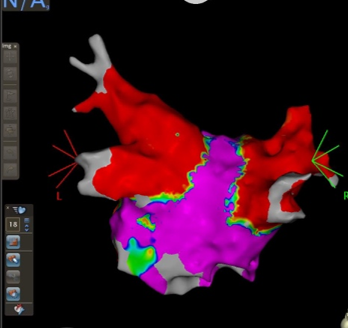

心房細動、心房粗動、発作性上室頻拍をはじめとした頻脈性不整脈に対して、洞調律維持を目指して、カテーテルアブレーションを中心とした治療を行っています。3次元マッピングシステムとして、CARTO®3およびEnSite™を用いて、放射線被ばくの低減や難治性不整脈に対する治療成功率の上昇を図っています。

CARTO®3での左房のVoltage Map

(左心房を後方から見た像)

症例患者様:70代 男性

症例治療内容:持続性心房細動に対して両側肺静脈隔離術

症例治療期間・回数:入院期間:3泊4日、手術時間:1時間30分、入退室2時間、初回症例